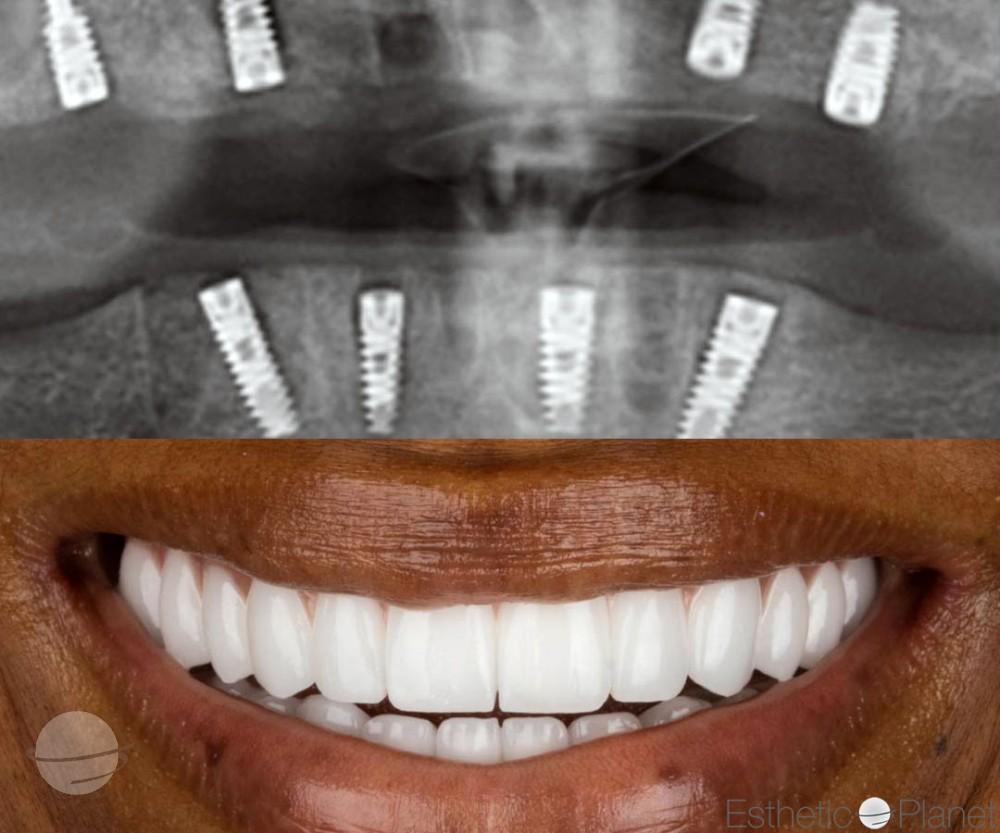

Résultat - Pack 8 Couronnes

Résultat - Pack 16 Couronnes

Résultat - Pack 20 Facettes

Résultat - Pack 8 Facettes

Résultat - Pack 16 Facettes